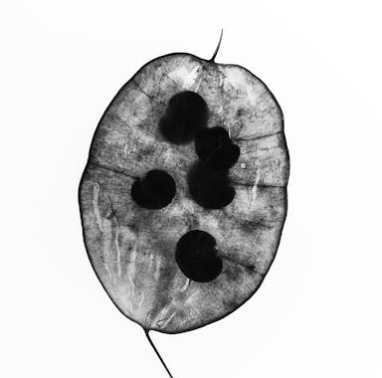

자궁은 내막, 근육층, 장막으로 이루어져 있는데, 정상적으로 자궁내막은 주기적으로 증식과 탈락을 반복하며 생리를 일으킵니다. 그러나 자궁선근증은 이 자궁내막 세포가 자궁 근육층으로 파고들어 증식하는 상태를 말합니다. 이로 인해 자궁벽이 두꺼워지고 자궁 자체가 커지면서 다양한 증상을 유발합니다.